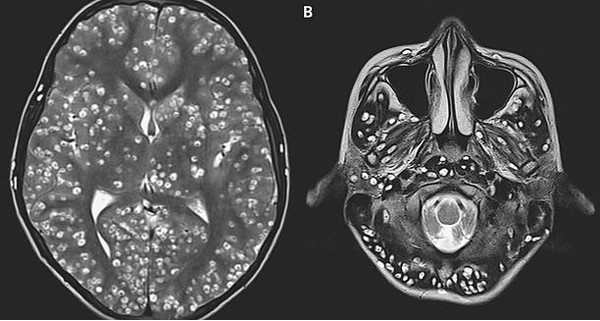

Kết quả chụp MRI cho thấy bệnh nhân có nhiều u nang trong vỏ não (hình bên trái là các chấm trắng). Các tổn thương cũng được tìm thấy trong thân não và tiểu não (hình phải)

| Sán làm tổ dày đặc trong não bệnh nhân. |

Kết quả chụp cộng hưởng từ trên bệnh nhân rất bất ngờ, bác sĩ phát hiện vô số u nang sán lợn trong vỏ não - vùng chịu trách nhiệm về suy nghĩ, trí nhớ, tri giác.